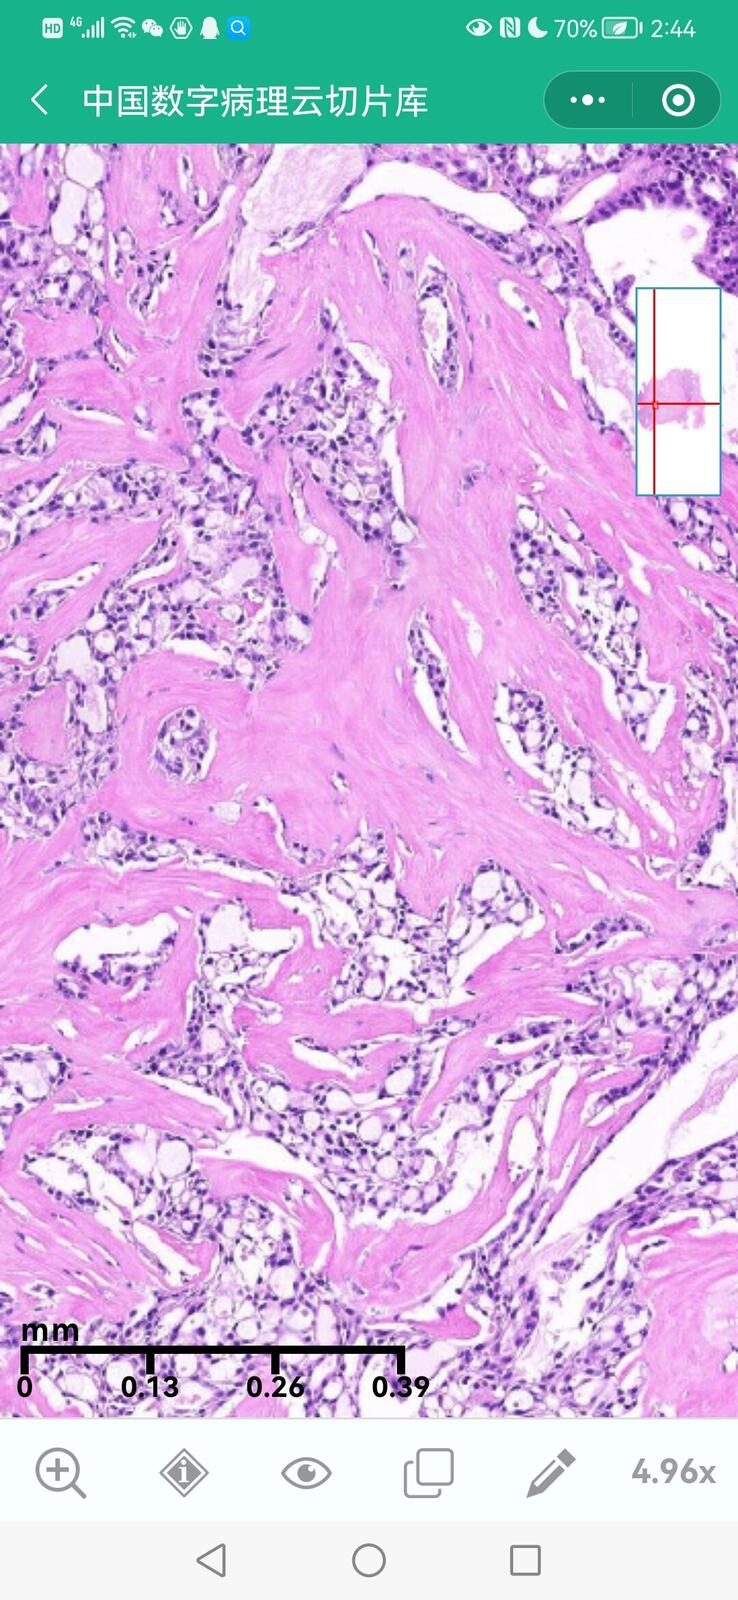

乳腺黏液性囊腺瘤伴导管内癌

乳腺多形性脂肪肉瘤

乳腺叶状囊肉瘤

乳腺分泌性癌(29岁)